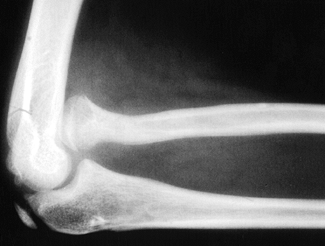

In CDRH, the radial head may be dislocated in an anterior, posterior,

or lateral direction; in one series, 47% were anterior, 43% posterior,

and 10% lateral (9).

The presenting complaint is usually posterolateral elbow prominence,

restricted elbow extension and forearm rotation, elbow “popping,” or

pain with activity (1,95),

although pain is uncommon before adolescence. Often, the limitations

due to CDRH are first perceived after an unrelated elbow injury and may

be erroneously attributed to that injury. When the condition is

unilateral, CDRH may be difficult to distinguish from chronic traumatic

dislocation (29) (Table 165.3).

the cubital fossa in anterior CDRH, and palpable and visible laterally

in posterior CDRH (see Fig. 165.27 and Fig. 165.28).

Elbow motion deficits are often minimal, usually nonprogressive, and

worse in anterior than posterior CDRH. Loss of supination is the most

prominent limitation in both anterior and posterior CDRH. Anterior CDRH

blocks full flexion, and posterior CDRH blocks full extension, causing

a flexion contracture (usually 30° or less). Wrist range of motion may

also be limited (1,9,97,111). In the infant, the unossified dislocated radial head may be visualized with diagnostic ultrasound (14), but the diagnosis is most commonly made by plain radiography (Fig. 165.27 and Fig. 165.28).

Figure 165.27. Anterior congenital dislocation of the radial head.

|